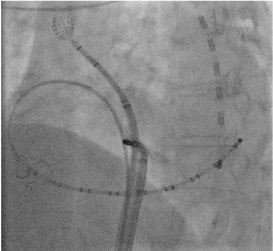

基本となる薬物療法に加えて、当院では高周波カテーテルアブレーションに力を入れています。当院のアブレーションは以下のような点で大きな進歩をしてまいりました。

• 心臓の形態や電位に関する情報をカテーテルを用いて把握

• コンタクトフォース(カテーテルによりかかる力)を可視化し適切な力で焼灼